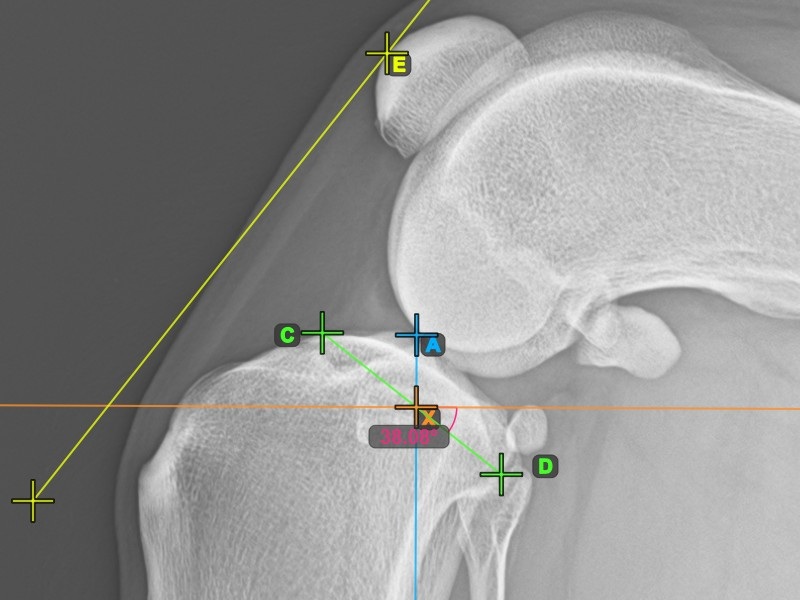

Start the TTA measurement procedure by marking the most cranial point of the Patella.

The image below depicts the usual placement of the most cranial point of the Patella.

To complete the TTA measurement procedure mark the most dorsal point of the Crista Tibiae (Tuberositas Tibiae). The distance between the Tuberositas Tibiae and the line passing along the most cranial point of the Patella is the required adjustment for the TTA procedure.

The image below depicts the usual placement of the tibial tuberosity, the most prominent point of the tibial crest.